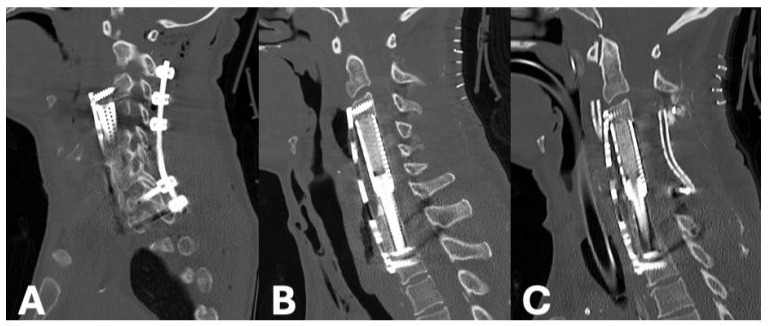

43-year-old female with past medical history significant for IVDU, chronic HCV, endocarditis, and depression returned to the hospital with a chief complaint of BLE paralysis and BUE paresis for two days. Past surgical history includes C6-C7 ACCF three months prior for MRSA osteomyelitis. Exam findings significant for 0/5 motor strength throughout BLEs and 2/5 throughout BUEs. CT Cervical Spine found fracture of the C5 vertebral body with hardware subsidence (Figure 5A). MRI Cervical Spine demonstrated significant canal stenosis with cord compression and large prevertebral abscess (Figure 5B). The patient was placed in cervical traction using Gardner-Wells tongs while in the emergency department. There was moderate improvement in cervical kyphosis, however no improvement in neurologic function. She was then taken to the operating room for revision ACCF extending from C4-T1 using an expandable titanium cage and C2-T2 posterior fixation. Post-operative CT Cervical Spine discovered significant displacement of the anterior hardware and dislodgement of cranial screws (Figure 6A). She returned to the operating room emergently for correction of hardware, with focus on maximizing purchase through increased screw length and diameter (Figure 6B). Postoperatively, the patient’s neurologic exam improved to antigravity throughout. Two days later, she experienced recurrence of BLE paralysis. MRI Cervical Spine discovered diffuse spinal cord swelling throughout the cervical region. She was taken emergently to the operating room for posterior cervical decompression which was completed without complications (Figure 6C). She returned to the intensive care unit intubated. Unfortunately, she soon thereafter developed septic shock from an intra-abdominal source and passed away two weeks later.

Figure 5: Sagittal CT Cervical Spine without Contrast demonstrating osseus destruction and focal cervical kyphosis above the corpectomy hardware (A). Sagittal T2 MRI Cervical Spine without Contrast showing significant cord compression (B).

Figure 6: Post-operative sagittal CT Cervical Spine without Contrast showing significant displacement of the anterior corpectomy cage and plate (A). Repeat CT completed after emergent revision of anterior hardware (B). CT Cervical Spine following posterior cervical decompression (C).